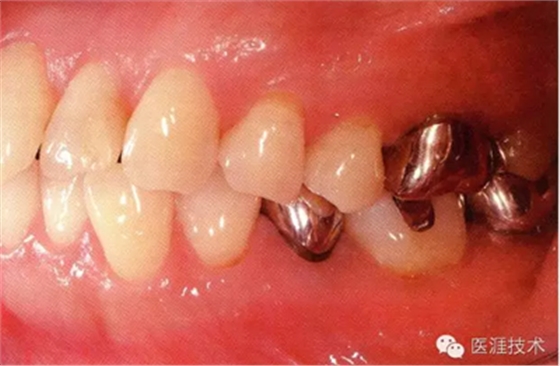

56歲牙周炎男性的臨床照片

正在服用高血壓藥中的56歲男性。菌斑控制得不好。通過(guò)牙周探診,全頜有4~6mm的牙周袋,在X光片中可以看到全頜中度牙槽骨吸收,磨牙處一個(gè)地方是重度牙槽骨吸收。通過(guò)比較牙周病進(jìn)展?fàn)顟B(tài),邊緣部有大范圍浮腫(發(fā)紅、腫脹),和纖維性肥厚。這也可能是服用中的降壓藥的副作用導(dǎo)致的。因?yàn)檠例l、牙槽骨比較厚,牙齦呈架子狀。